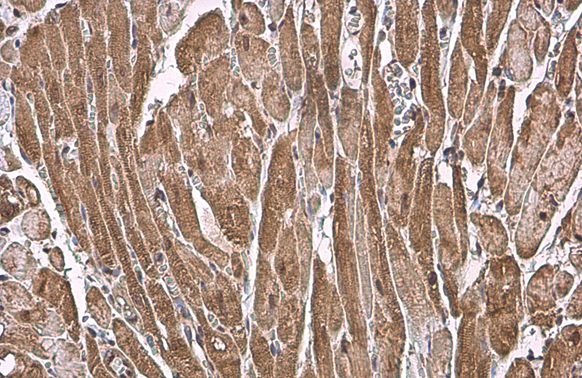

![ANP antibody [HL2617] detects ANP protein by immunohistochemical analysis. Sample: Paraffin-embedded mouse tissues. ANP stained by ANP antibody [HL2617] (GTX639071) diluted at 1:100. Antigen Retrieval: Citrate buffer, pH 6.0, 15 min ANP antibody [HL2617] detects ANP protein by immunohistochemical analysis. Sample: Paraffin-embedded mouse tissues. ANP stained by ANP antibody [HL2617] (GTX639071) diluted at 1:100. Antigen Retrieval: Citrate buffer, pH 6.0, 15 min](https://www.genetex.com/upload/website/prouct_img/normal/GTX639071/GTX639071_T-45173_20230928_IHC-P_multiple_M_23103019_769.webp)